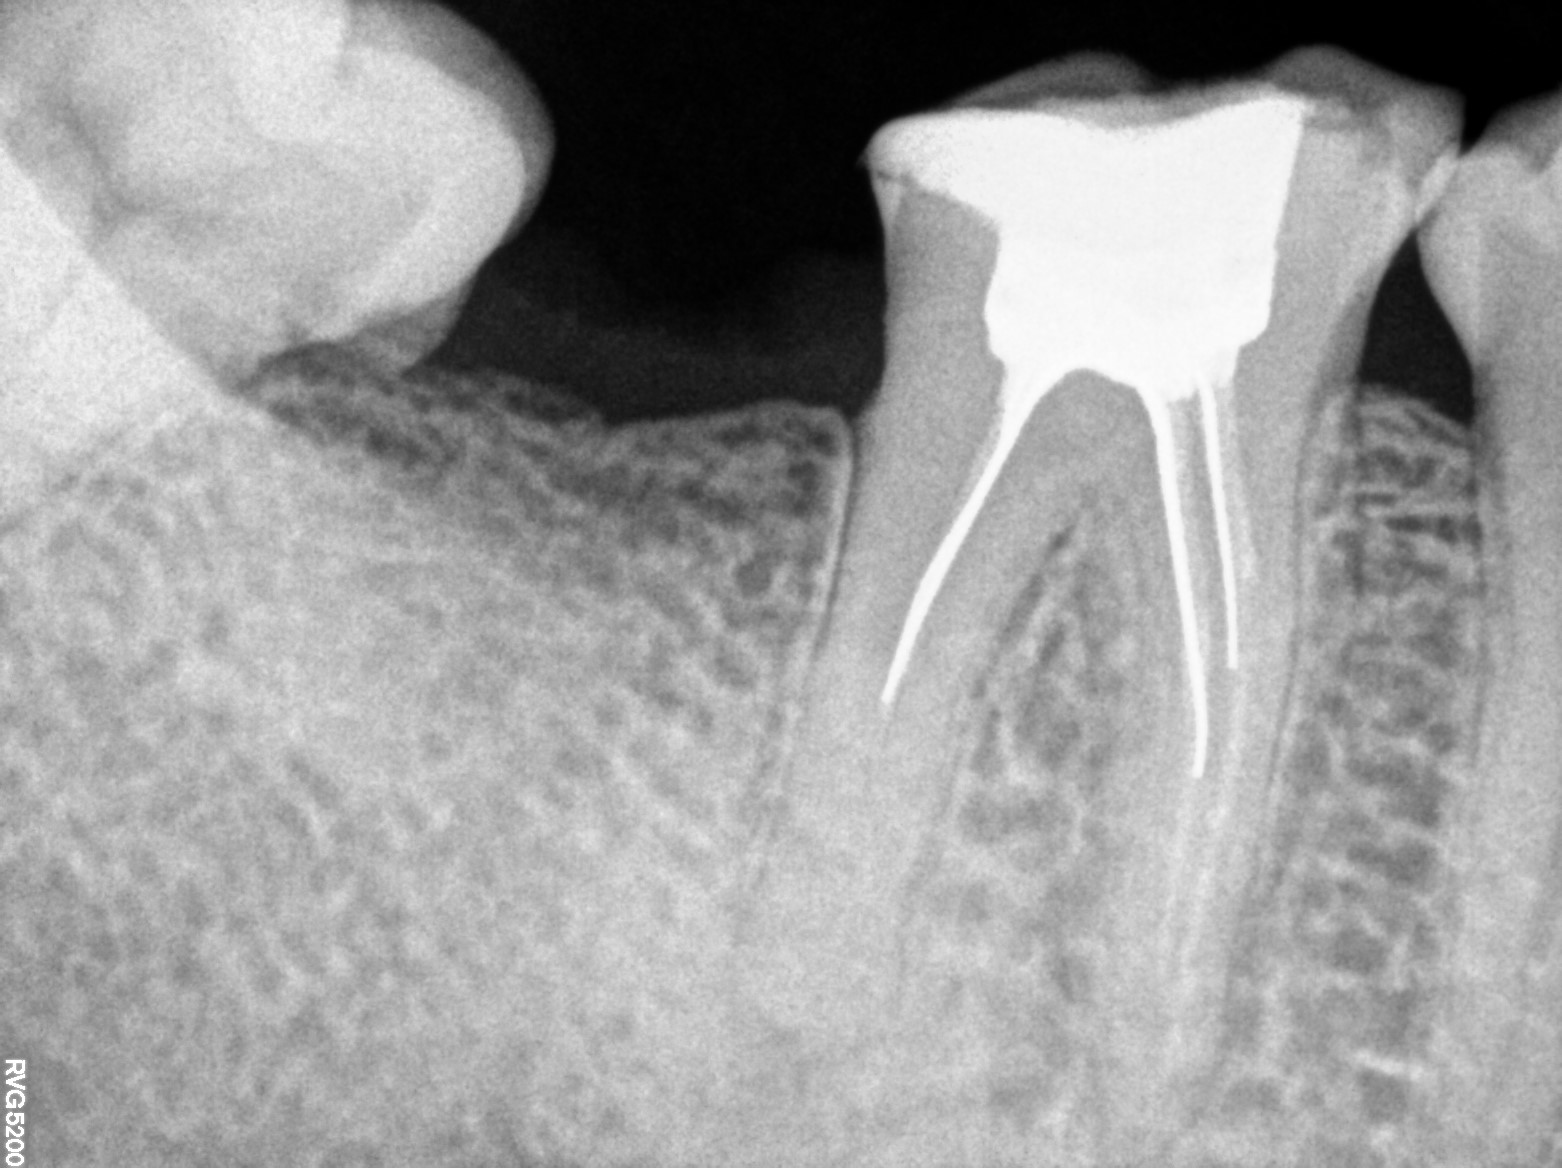

Dental Radiographs FHIR: DocumentReference · LOINC 24641-7

R53.jpg

24641-7

| Root canal treatment | 234780006 | D3330 Endodontic therapy, molar tooth | ##17, #46 | 2023-03-06 | completed | all metal crown preparation with 17 & 46 and D-tech done with 17 impression recorded & root canal treatment done elsewhere & | |

| Necrosis of dental pulp | K04.1 | 234946006 | resolved | 2023-03-06 | all metal crown preparation with 17 & 46 and D-tech done with 17 impression recorded & root canal treatment done elsewhere & | |

| Crown of tooth | 424311000 | D2750 Crown, porcelain fused to high noble metal | ##17, #46 | 2023-03-09 | completed | crown cementation done with 17 & 46 | |

| Dental caries | — | 80967001 | resolved | 2023-03-09 | crown cementation done with 17 & 46 | |